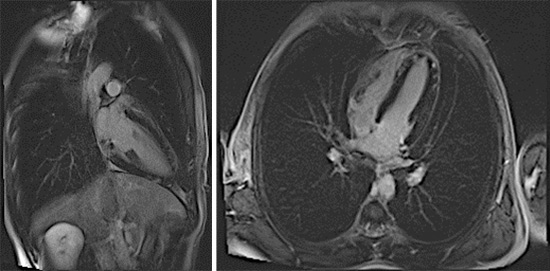

Figure 2 : Séquence T2 STIR, coupes petit-axe

Figure 3 : Séquence T2-mapping, coupes petit-axe

Figure 4 : Séquence de Réhaussement tardif

Coupes petit-axe

Coupes long-axe 2 cavités et 4 cavités

Cinétique du VG normale mais présence d’une prise de contraste sous-épicardique diffuse.

Myocardite aiguë étendue à la paroi inféro-latérale et latérale débordant en septo-apical.

- La topographie sous-épicardique du réhaussement tardif est très en faveur d’une pathologie inflammatoire évocatrice de myocardite.

- La présence de l’œdème myocardique sur les séquences de T2-STIR et T2 mapping traduit un phénomène inflammatoire récent dans les 4 dernières semaines.